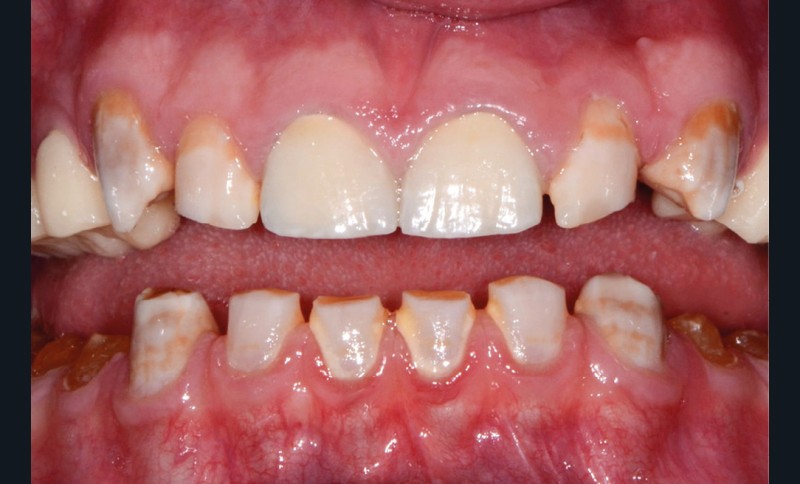

Avant tout traitement, il convient de déterminer l’étiologie des colorations dentaires. Selon leur origine, la stratégie thérapeutique et les informations délivrées au patient peuvent différer. Outre les modifications de couleur inhérentes au vieillissement des dents (fig. 1a), on distingue généralement deux types de dyschromies selon que leur étiologie est intrinsèque ou extrinsèque [2].

Elles sont causées par des agents colorants externes qui se déposent généralement sur la surface amélaire. Leurs origines sont diverses : alimentation (fig. 1b), tabac (fig. 1c), plaque bactérienne ou bactéries chromogènes (fig. 1d), ainsi que certains médicaments. La réalisation d’un aéropolissage en complément du détartrage initial est généralement suffisante pour éliminer efficacement ces colorations. Cependant, le patient doit être prévenu qu’en l’absence de modification de ses habitudes de vie, celles-ci reviendront [2, 4].